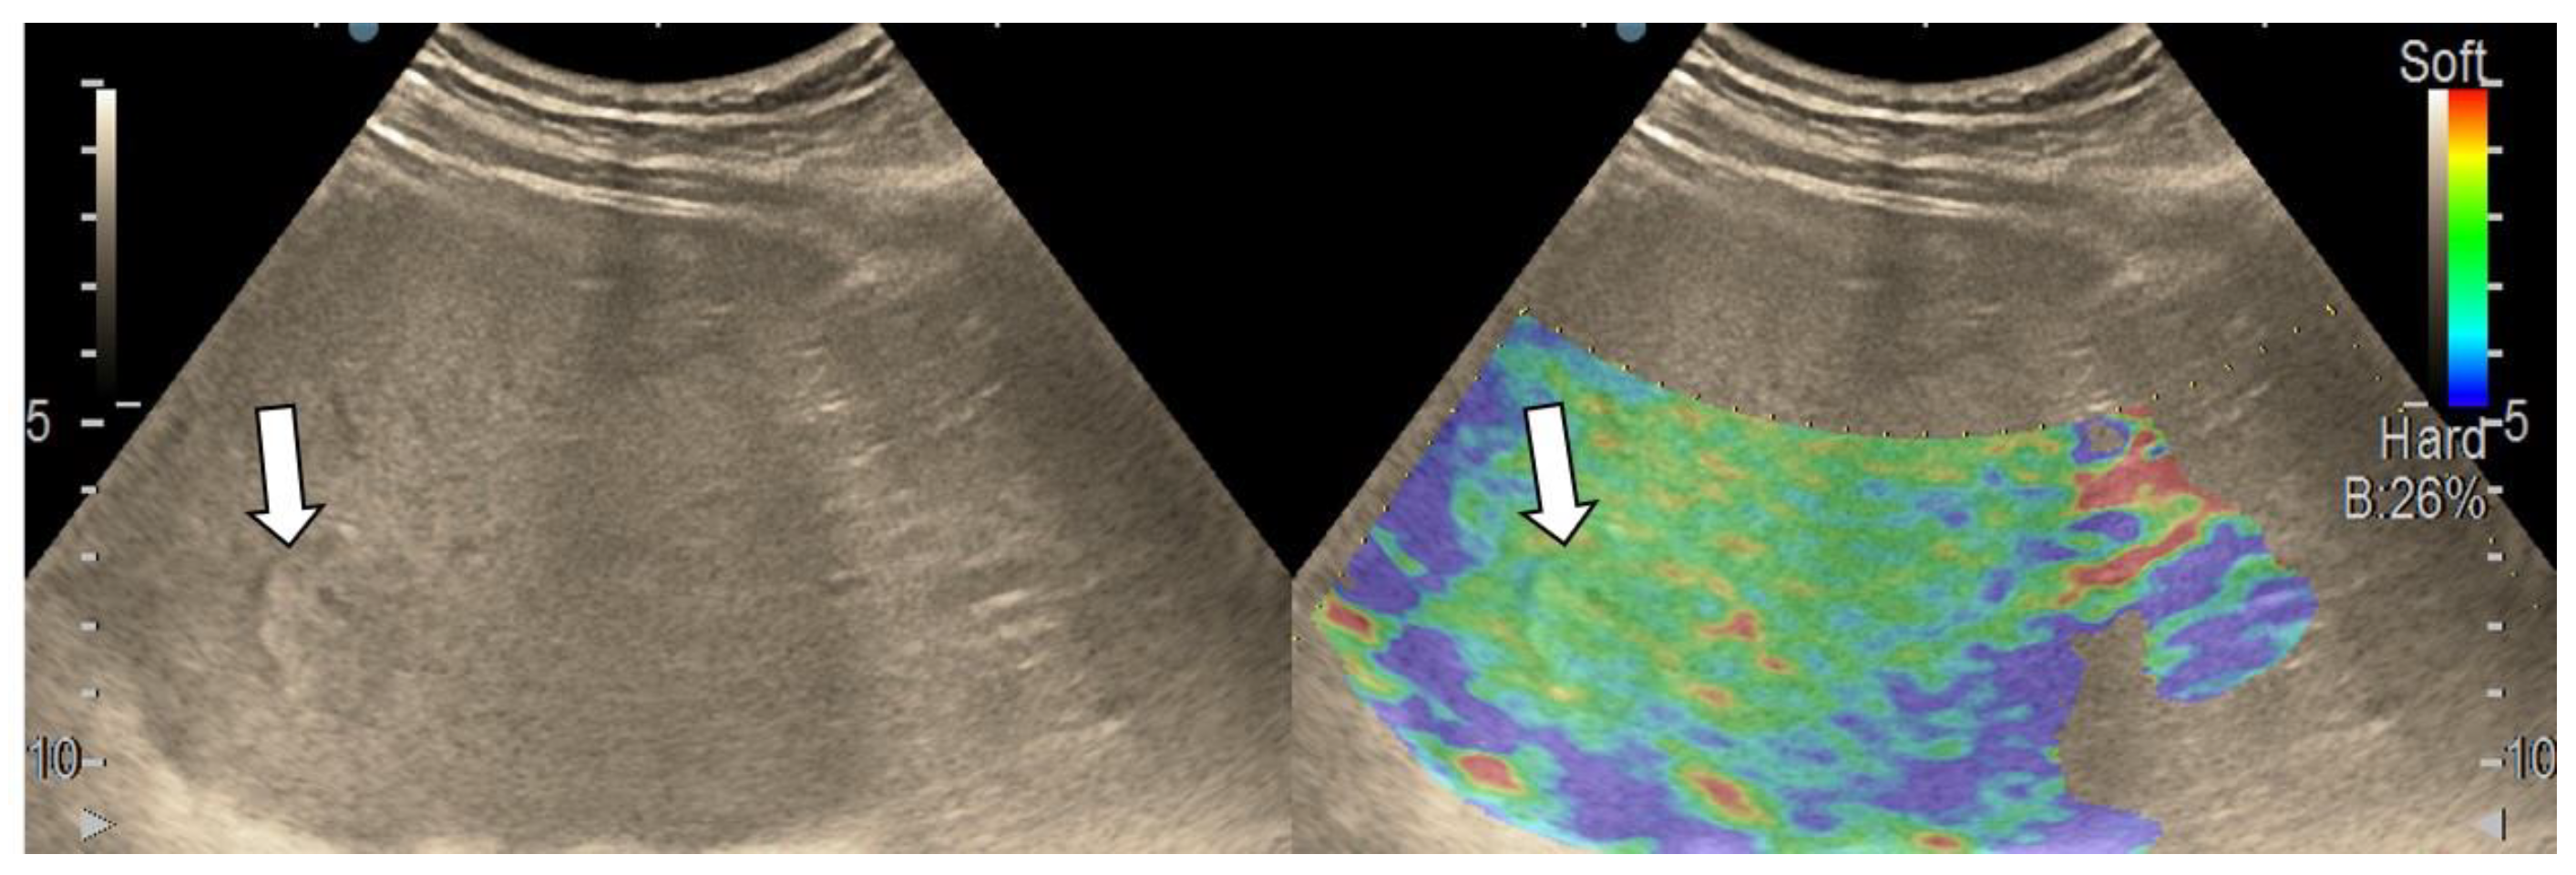

3.1. B-Mode Ultrasound

3.4. Real-Time Tissue Elastography